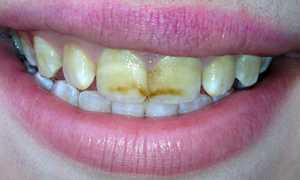

- В случае скопления остатков пищи в полости зуба и недостаточном уходе за полостью рта появляется так называемый галитоз (резкий неприятный запах из полости рта).

Хронический фиброзный пульпит представляет собой воспаление зубной пульпы, которое может развиваться в результате длительного воздействия кариеса или травмы зуба. Врачи отмечают, что основными симптомами являются периодические боли, особенно при воздействии на зуб горячей или холодной пищи, а также возможное изменение цвета зуба. Причинами заболевания чаще всего становятся запущенные кариозные процессы и недостаточная гигиена полости рта.

Хронический фиброзный пульпит — это воспаление зубной пульпы, которое может развиваться на фоне запущенного кариеса или травмы зуба. Люди часто отмечают такие симптомы, как постоянная боль, особенно при воздействии холодного или горячего, а также повышенную чувствительность зубов. Причинами заболевания могут быть бактерии, механические повреждения или химические раздражители.